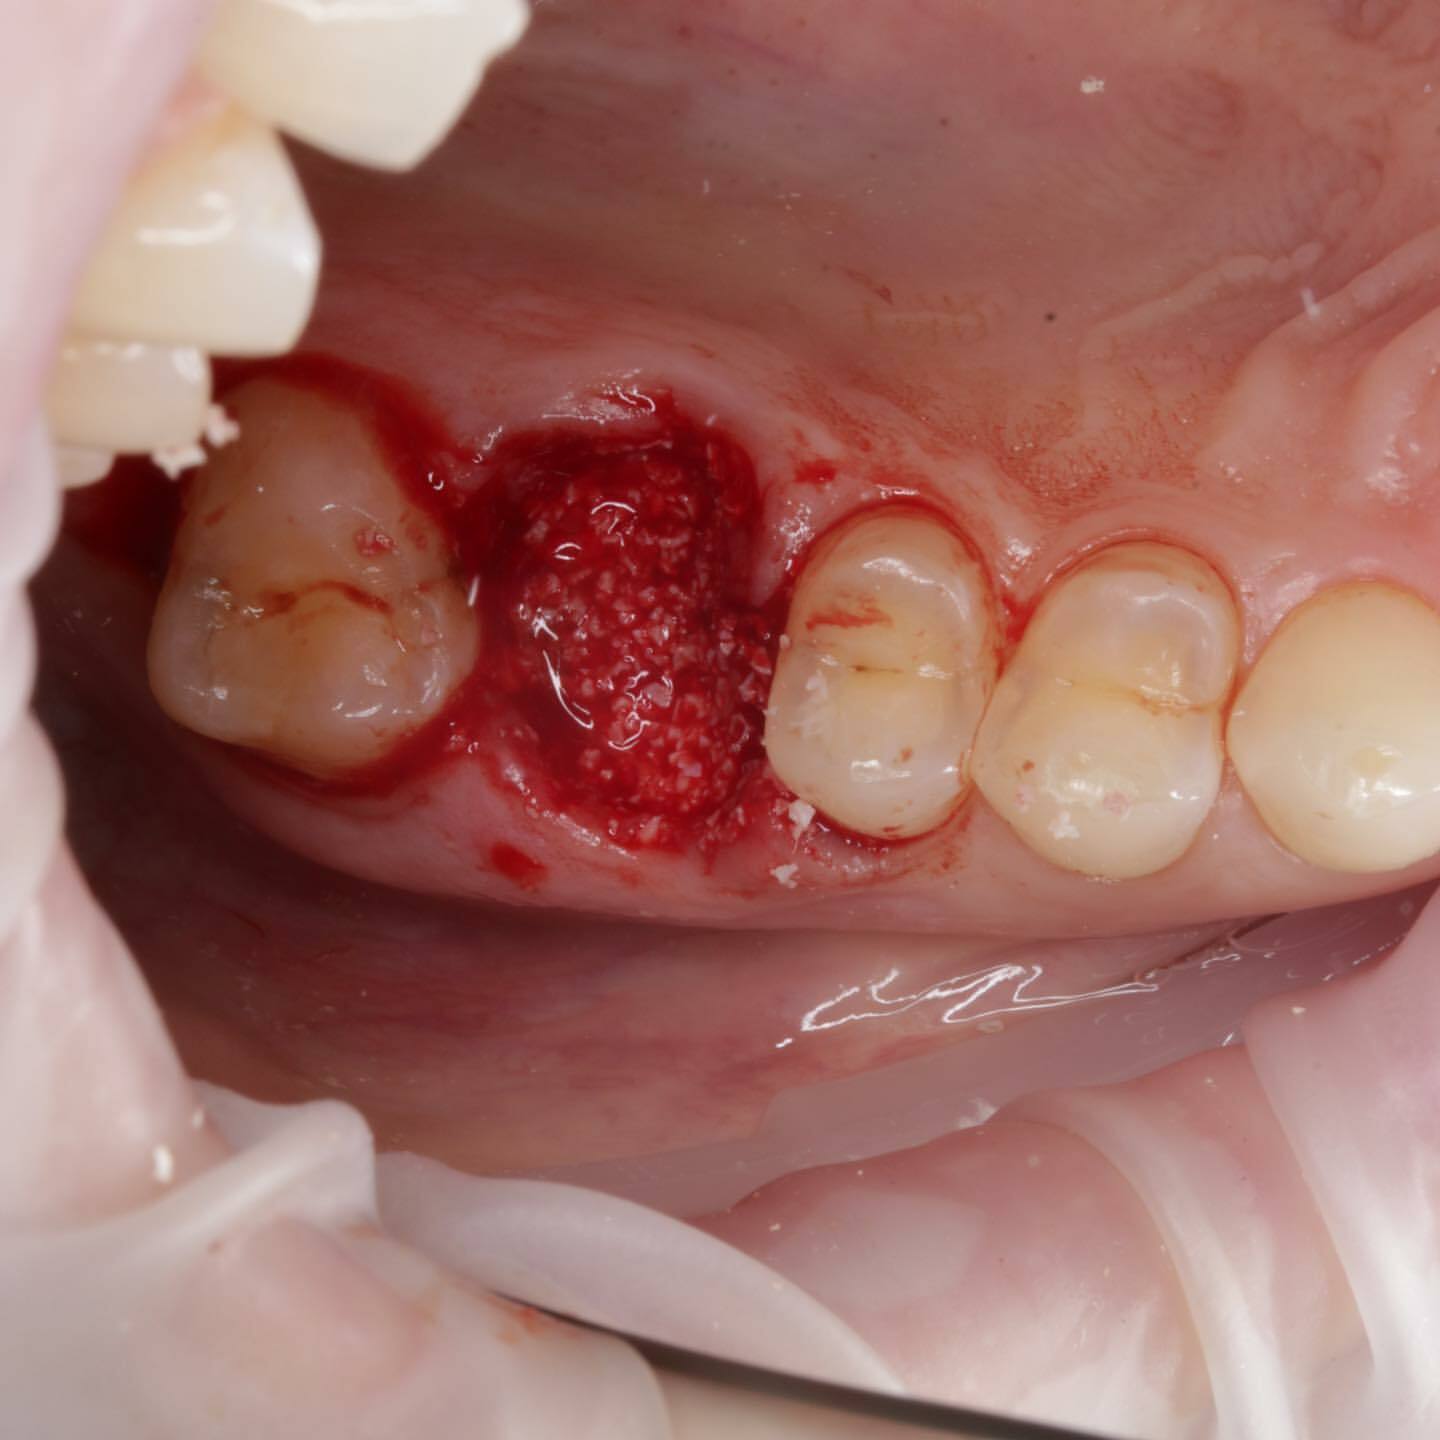

Период «без зуба» существенно сокращается или вовсе отсутствует. Так как в классическом протоколе после удаления мы ждём 2-3 месяца, потом ставим имплантат и ждём его остеоинтеграции 3-4 месяца. Только после этого приступаем к изготовлению коронки.

При одномоментном протоколе мы ускоряем весь процесс на 2-3 месяца! То есть после удаления и одномоментной имплантации мы ждём только 3-4 месяца 🥳

Вместо двух операций (сначала удаление, а спустя два-три месяца имплантация) проводится одна двойная операция. И, соответственно, вместо двух послеоперационных периодов получается один.

🟢 НЕТ ПОТЕРИ КОСТНОЙ ТКАНИ

При классической имплантации в период между удалением и имплантацией костная ткань, так необходимая для успешной приживаемости имплантата, остается без нагрузки, поэтому неизбежно уменьшается в объеме. Одномоментная имплантация позволяет этого избежать.